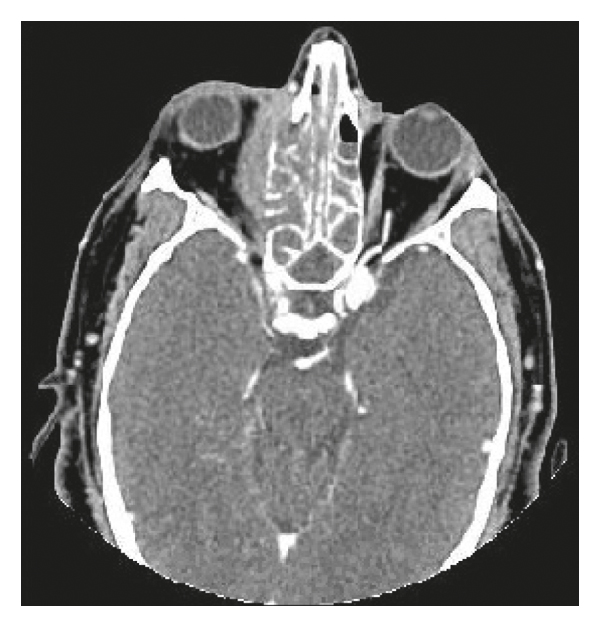

A 44-year-old Hispanic male from Mexico presented to the emergency department for progressive nasal congestion, rhinorrhea, ear fullness, facial swelling, and sore throat that has been ongoing for 2 months. He also noted gradual vision loss of his right eye and intermittent bloody discharge from both the nostrils. Bedsides, rhinoscopy showed swelling of the right nare and nasal turbinates along with small blood clots without active bleeding. A maxillofacial computed tomography (CT) scan showed phlegmonous change about the right lamina papyracea with an erosive change. Also shown was destruction and soft-tissue swelling that extends along the medial border of the right orbit (Figure 1). Biopsy of the right nasal vestibule was diagnostic for extranodal NK/T-cell lymphoma nasal type. The atypical cells were positive for CD2, CD3, CD4, CD56, CD43, and Bcl-2 and negative for CD5, CD7, CD8, CD10, CD20, CD30, and BCL-6. In situ hybridization was positive for the Epstein–Barr encoding region (EBER). Bone marrow biopsy showed a normocellular bone marrow with trilineage hematopoiesis. Additional imaging with magnetic resonance imaging (MRI) of the head showed a vague enhancement over the frontal convexities. EBV DNA PCR in the blood was 4.90 log10 IU/mL (equivalent to 79,792 IU/mL). He was started on a modified SMILE (m-SMILE) regimen consistent of methotrexate 2 g/m2 given on day 1, etoposide 100 mg/m2, ifosfamide 1500 mg/m2, dexamethasone 40 mg/d given on days 2 to 4, and pegasparagase 2000 U/m2 given on day 8 of a 28-day cycle (Figure 2). He developed acute right-sided complete vision loss; magnetic resonance imaging of the orbits showed increased enhancement of the optic nerve sheath with a complex edema suspicious for optic nerve invasion. The case was discussed at an ENT oncology and other multidisciplinary oncology conferences; the decision was made to proceed with the same chemotherapy regimen. The patient then received prophylactic intravitreal methotrexate of the left eye. He completed his second cycle of m-SMILE, and a follow-up positron emission tomography-computed tomography (PET/CT) scan showed good response (Figure 3(a)). Methotrexate dose had to be reduced 50% on the third cycle of m-SMILE due to kidney injury. He subsequently received 4 more cycles of m-SMILE with 25% dose reduction of chemotherapeutic agents due to prolonged cytopenia from previous cycles. His EBV DNA PCR turned undetectable after the first cycle and remained so after the final (6th) cycle. A restaging PET/CT scan showed good response with faint residual disease in the paranasal sinuses and sinonasal cavity (Figure 3(b)). One month after he completed his last cycle, he developed new-onset severe headache, confusion, and shortness of breath. He was admitted to the emergency department where a CT scan of the head showed diffuse cerebral and cerebella edema. MRI of the brain with intravenous contrast revealed multiple focal cortical and subcortical signal abnormalities, with extensive gyral swelling involving the frontal, anterior parietal, and bilateral temporal lobe. Subtle enhancement in the sulci of the high frontoparietal region, particularly at the central sulcus, was noted (Figures 4 and 5 ). Cerebrospinal fluid examination was positive for CD 56+ cells and aberrant atypical lymphocytes. EBV DNA PCR was 14,800 IU/mL. His course was later complicated by respiratory failure and cerebellar tonsillar herniation; he subsequently succumbed after 19 days of hospitalization.